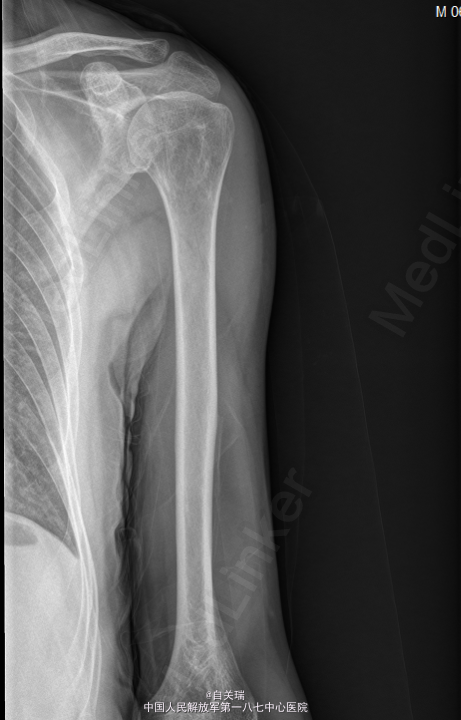

患者,男,63岁,因“发现左上臂肿块10余年左手内侧麻木1年”入院。 患者10多年前无意间发现左上臂近端内侧有一肿块,无明显压痛,无红肿,未给予重视。近1年左右肿块有所增大,触摸可出现左手内侧麻木,肢端血供正常,无明显肌肉萎缩。

左上臂近端内侧可及约4CM*5CM的肿块,质韧,周围皮肤无红肿,触摸可出现左手内侧麻木,未见有肌肉萎缩,肢端血供感觉良好。MRI: 左上臂上段内侧皮下良性占位,神经鞘瘤可能.